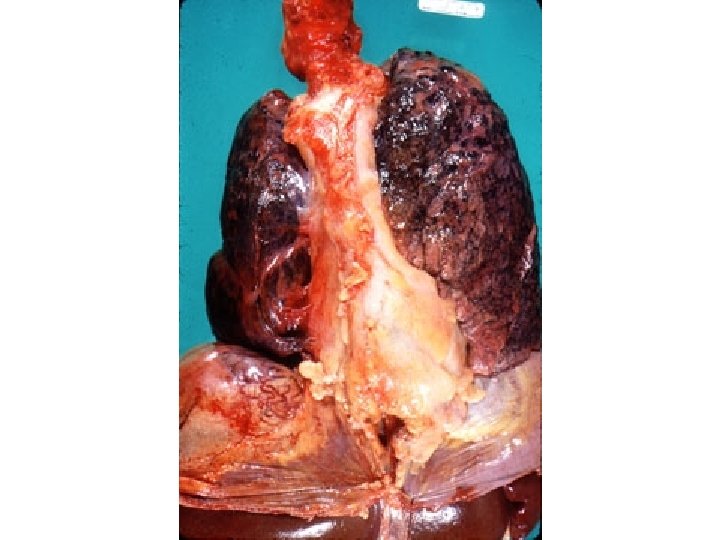

Consolidation

Pneumonia

Air bronchogram Lobar No loss of volume Consolidation